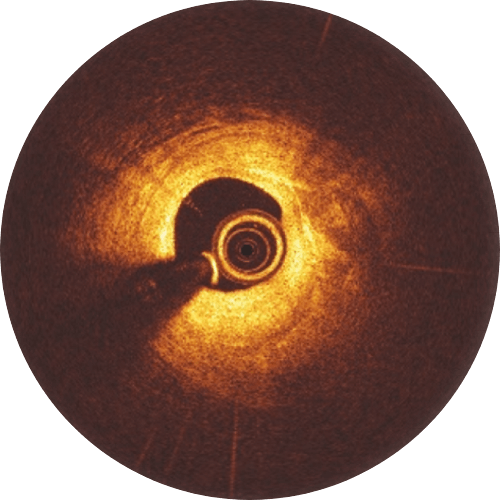

12-month follow-up

The Magnesium resorption is completed. No struts appear in OCT.

>99%

of struts no longer visible at 12 months8

Magnesium fully resorbed after 12 months8